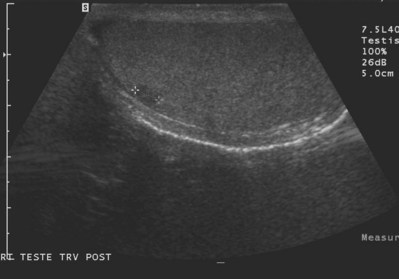

Scrotal ultrasound for the infertile male is primarily used to confirm the presence of clinical varicoceles, although it also provides high-quality imaging of scrotal contents that offers the advantage of widespread availability without exposure to ionizing radiation. Although clinical varicoceles do not require confirmation with ultrasound examination, color Doppler ultrasound may be required when the clinical examination is difficult due to body habitus or when the examination is equivocal. Demonstration of reversal of venous blood flow with the Valsalva maneuver or spermatic vein diameters of 3 mm or greater (Fig. 21–3A and B) support the diagnosis of varicocele (Meacham et al, 1994). Scrotal ultrasound is not recommended for screening for subclinical varicoceles because repair of these has not been demonstrated to be of clinical benefit.